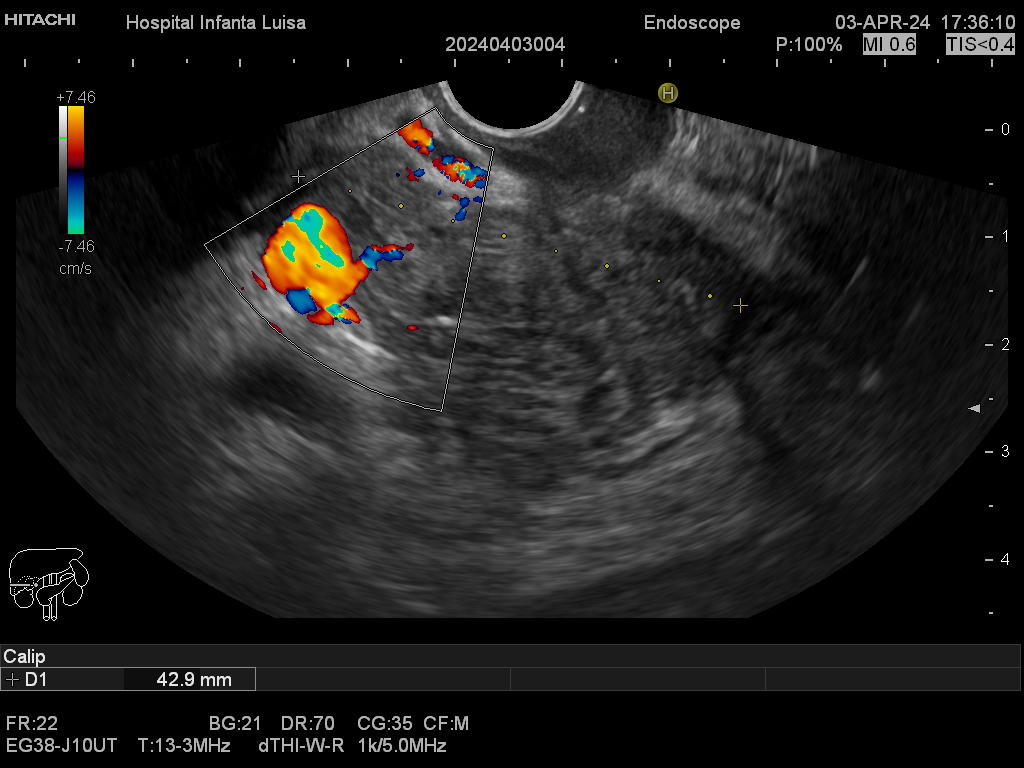

Mediante dicha exploración se explora minuciosamente los tramos mencionados, permitiendo valorar distintas patologías como lesiones propias de la pared de estos órganos (determinado su profundidad y extensión), o lesiones que quedan en órganos anexos, pero por fuera, de ahí la importancia de la visualización ecográfica, como páncreas, mediastino, hígado, diferentes adenopatías o masas indeterminadas previamente, entre otros.

Igualmente, es una técnica básica hoy día en el estudio de todo tipo de lesiones pancreáticas, en la determinación de formaciones subepiteliales esofágicas, gástricas (más frecuentes) o duodenales, o en el estadiaje de patología tumoral a estos niveles. La Ecoendoscopia permite la toma de biopsias a estos niveles, con control endoscópico y ecográfico, siendo una técnica de gran rentabilidad diagnóstica y seguridad.